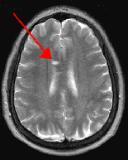

By turning CSF dark, bright periventricular lesions such as MS plaques become much more conspicuous. Fig. 1 shows a typical T2-weighted axial image of the brain in which CSF in the ventricles appears bright. A lesion on the right is present (red arrow) that is also bright similar to CSF. Fig. 2 is a corresponding FLAIR image showing an obvious bright MS plaque (white arrow) against a background of dark CSF and gray parenchyma with additional more subtle lesions.